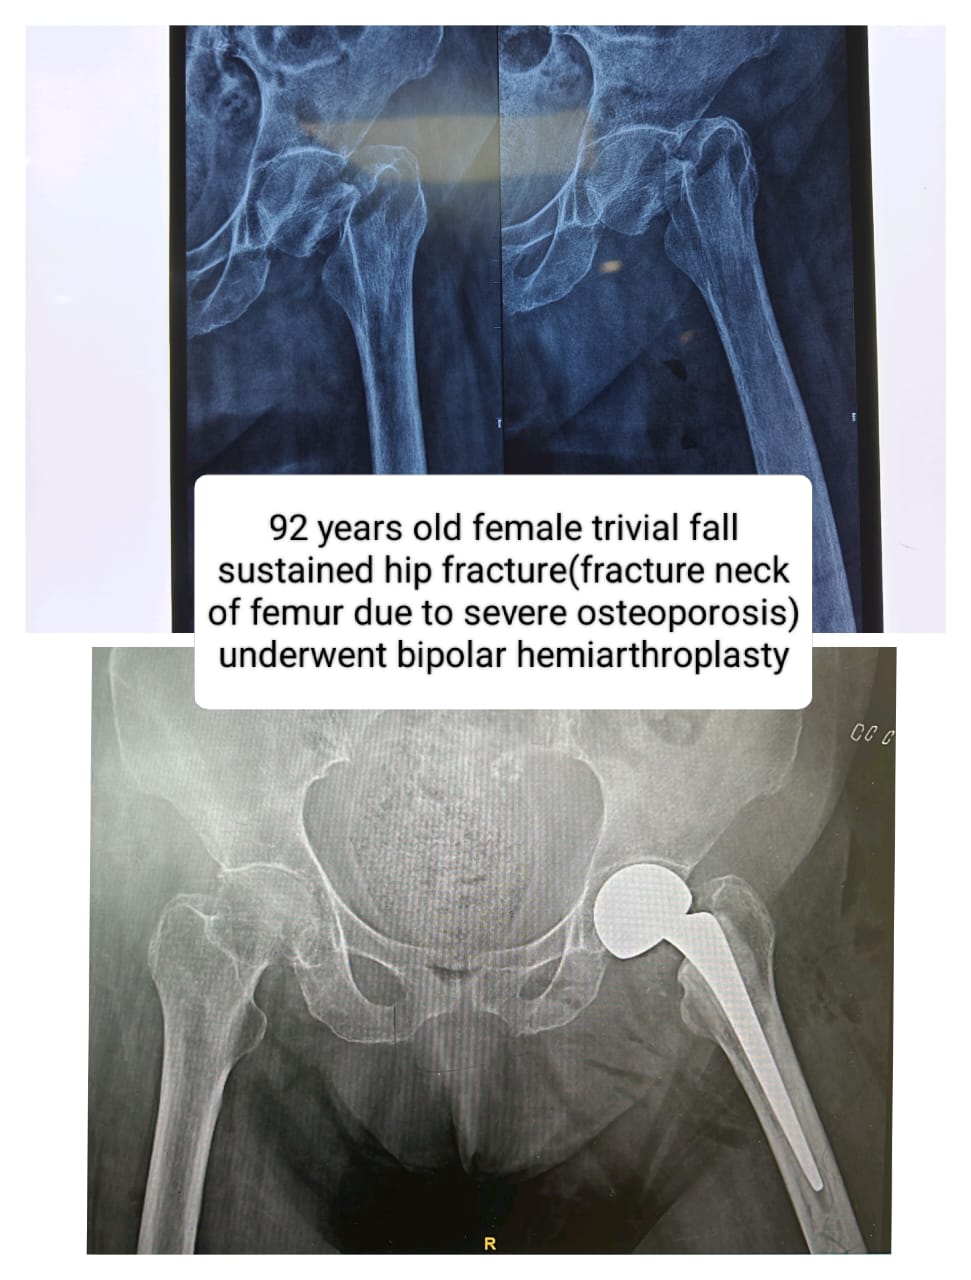

Case Study

Osteoporotic Neck of Femur Fracture: Successful Treatment and Recovery at Vyom Ortho Care